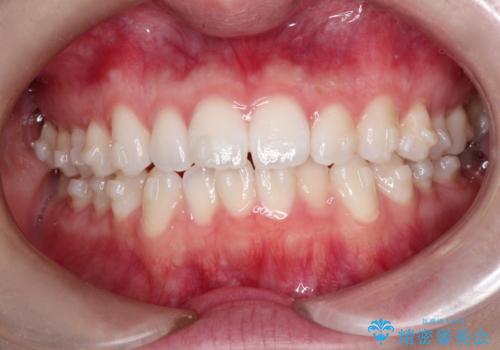

- 上下の前歯の凸凹が気になり、来院されました。

インビザラインで綺麗に仕上がり、満足していただきました。